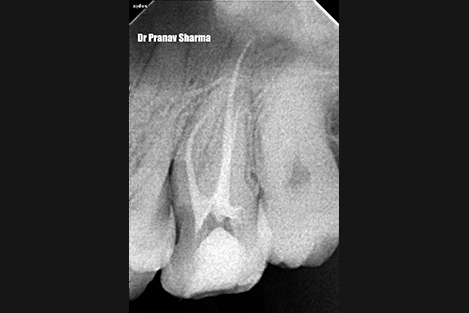

Xray